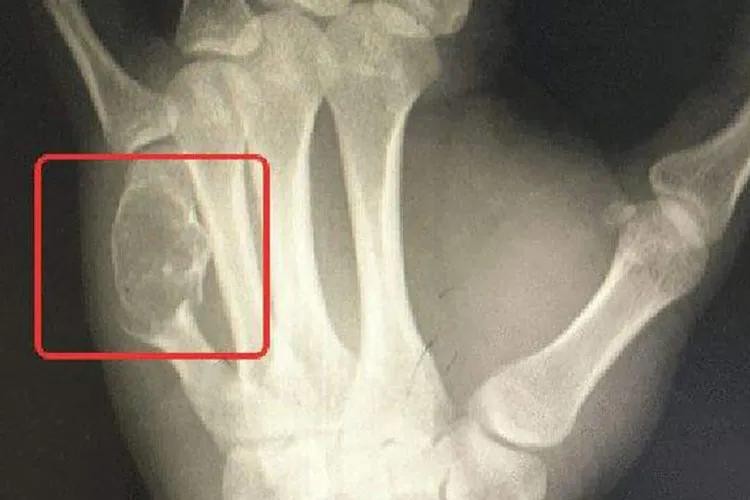

许多骨癌早期并没有典型的症状表现,少数骨癌的早期可出现疼痛症状,开始为间歇性,后来发展为持续性,夜间较明显,晚期疼痛加重。有的病人因疼痛剧烈而抱肤辗转,彻夜不能安眠,疼痛如针刺、刀割、火烧、钻痛,邻近关节有放射性疼痛,影响工作和休息。患者自感肢体疼痛,与肿胀或肿块的部位一致,具有固定性、持续性的特点,甚至服用镇静药无效。一般症状与其他癌症病者一样有食欲减低、体重减轻、发烧等症状。逐渐发展患部之关节与肢体运动受限制,患部皮肤溃烂,肢体远端会有麻木感,甚至发生病理性骨折或变形。

骨癌可通过病史、体格检查及辅助检查来进行诊断。体检检查及X线检查可判断肿瘤部位;CT及MRI检查可显示肿瘤软组织侵犯和髓腔浸润程度;肺CT判断有无肺转移;骨扫描排除骨转移;病理学检查为骨癌确诊依据,通过针吸活检或切开活检进行病理检查,可以明确诊断并进一步确定肿瘤亚型。